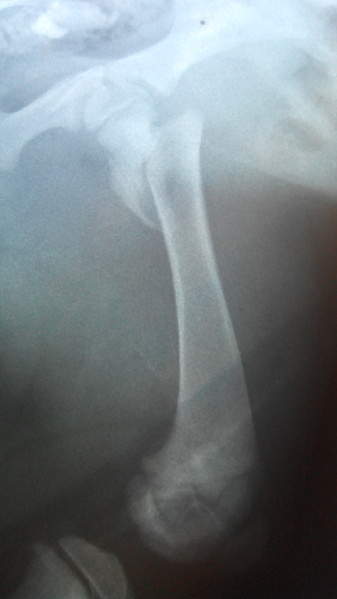

Здравствуйте. Ситуация: щенок 2 мес. лайка перелом левого тазобедренного сустава. Чрезвертельный перелом бедра со смещением кпереди на толщину кости и вверх на 1 см.